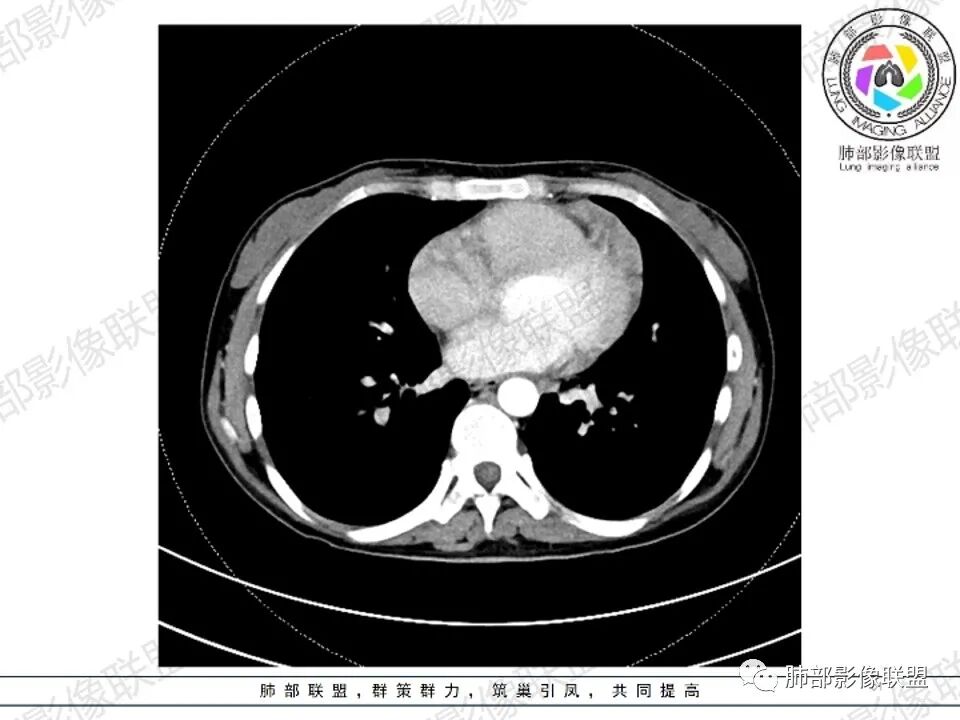

2.影像显示前纵隔不规则块状影,依势贴附心脏大血管旁,密度不均,边界不甚清楚,有结节融合感。

3.病灶轻度不均匀强化,可见血管穿行,散在液性低密度区。

双肺门未见肿大淋巴结。

4.双侧腋窝区见增大淋巴结,边界清楚。

3、影像学表现:显著肿大强化的淋巴结,常局限性分布;当患者无或仅轻微症状,纵隔内和腹膜后出现单个慢性巨大肿块,CT平扫示肿块边缘清楚,实质密度均匀,尤其是肿块呈显著强化和邻近大血管一致时,提示本病的可能。即使实质密度不均匀,中心液化坏死,但实质部分呈显著强化,与邻近大血管相似时,在鉴别诊断中仍然要考虑到本病的可能。